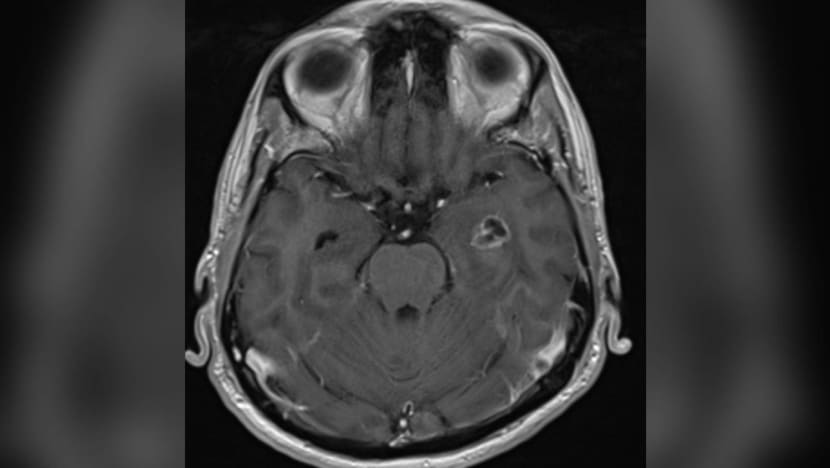

Mr Sadayan Ahmed Maideen Jabbar, who underwent two surgeries for glioblastoma in July 2021, and a scan showing a tumour growing on a part of his brain. (Images: NUH, Cheryl Lin)

Measuring 2.5cm in its diameter, the tumour was not large, said Dr Yeo Tseng Tsai, the head of NUH’s neurosurgery department.

But it was located at the amygdala, which Dr Yeo described as “the emotional part of the brain responsible for rage, anger, your fight or flight response”.

“It’s a very primitive part of the brain … I think the location of this tumour has probably caused him to behave the way he has.”